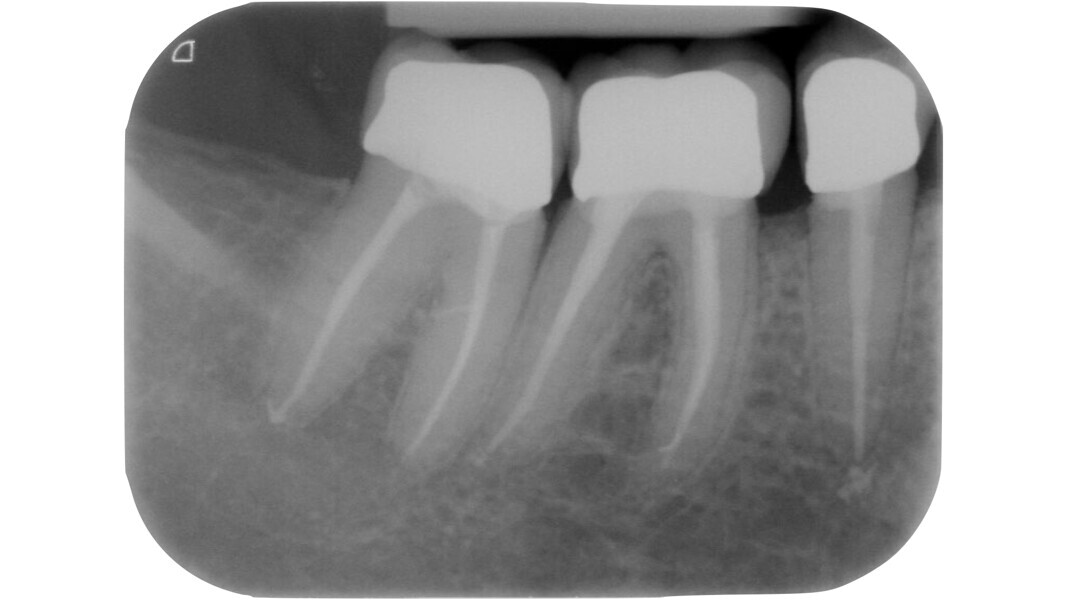

Fig. 13 : Emplacement des mesures effectuées par Deutsch et al.8, 9 sur une molaire inférieure analysée par micro-TDM (avec l’aimable autorisation du Prof. Elio Berutti).

Dans les molaires, la distance entre la pointe d’une cuspide et le plafond de la cavité pulpaire est d’environ 6,3 mm, tandis que dans les prémolaires supérieures, elle est de 6,94 mm. La cavité pulpaire a une hauteur d’environ 1,5 à 2 mm et la distance moyenne entre le plancher de la cavité et la furcation est d’environ 3 mm (Tableau 1) (Fig. 13).